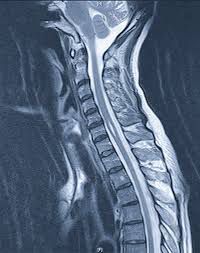

Treatment Treatment for syringomyelia depends on the severity and progression of your signs and symptoms. Monitoring If syringomyelia isn't causing signs or symptoms, monitoring with periodic MRI and neurological exams might be all you need. Surgery If syringomyelia is causing signs and symptoms that interfere with your life, or if signs and symptoms rapidly worsen, your doctor will likely recommend surgery. The goal of surgery is to remove the pressure the syrinx places on your spinal cord and to restore the normal flow of cerebrospinal fluid. This can help improve your symptoms and nervous system function. The type of surgery you'll need depends on the cause of syringomyelia. To reduce pressure on your brain and spinal cord, surgery options include: Treating Chiari malformation. If syringomyelia is caused by Chiari malformation, surgery might involve removing a small section of bone at the back of your skull. This surgery can reduce pressure on your brain and spinal cord, restore the normal flow of cerebrospinal fluid, and might improve or resolve syringomyelia. Draining the syrinx. Your doctor will surgically insert a drainage system, called a shunt. It consists of a flexible tube that keeps fluid from the syrinx flowing in the desired direction. One end of the tubing is placed in the syrinx, and the other is placed in another area of your body such as your abdomen. Removing the obstruction. If something within your spinal cord, such as a tumor or a bony growth, is hindering the flow of cerebrospinal fluid, surgically removing the obstruction might restore the flow and allow fluid to drain from the syrinx. Correcting the abnormality. If a spinal abnormality is hindering the flow of cerebrospinal fluid, surgery to correct it, such as releasing a tethered spinal cord, might restore fluid flow and allow the syrinx to drain. Surgery doesn't always restore the flow of cerebrospinal fluid, and the syrinx might remain, despite efforts to drain the fluid from